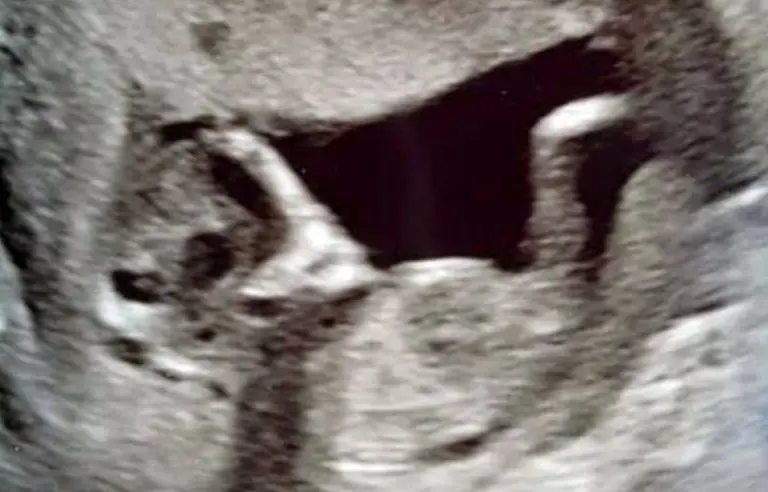

تصویر عکس سونوگرافی یک جنین مادرش را ترساند.

ماجرا از آن قرار است که مادری جوان در انگلیس در سونوگرافی اخیرش با صحنهای عجیب و ترسناک در رحمش مواجه شد که تصمیم گرفت آن را در فضای مجازی انتشار دهد.

سوفی اسکات ۱۶ ساله و استیفن ۲۴ ساله زمانی که برای سونوگرافی به پیش پزشک رفتند با صحنهای عجیب در شکم سوفی مواجه شدند که آنها را تاحدودی ترساند.

در شکم سوفی دو چشم عجیب و ترسناک جنین به چشم میخورد که به شدت به موجودات فضایی شباهت دارد به همین منظور موجب ترس و وحشت آنها شده است.

به گفته سوفی: من ترسیدم که این موجود بیگانه جنین من را خورده باشد و این چشمان چشمهای یک موجود فضایی به جای دخترم در شکمم باشد.